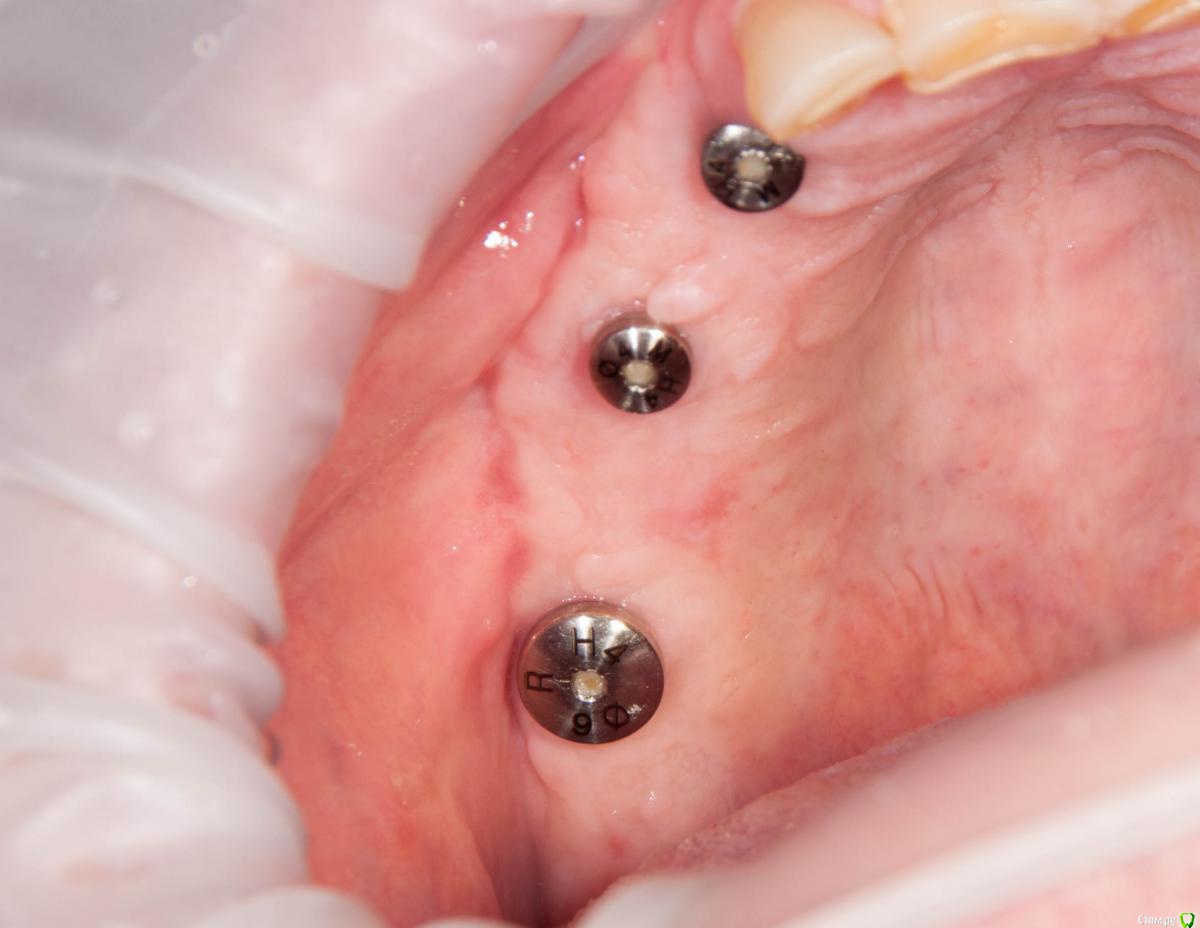

kamranchick Опубликовано 4 мая, 2018 Поделиться Опубликовано 4 мая, 2018 Обратился пациент после очередной халтуры которыми радуют меня коллеги из соседних клиник)фотопротокол ни как у Сашки Гудкова но более-менее понятно))Обратился пациент, в соседней клинике удаляли зуб, корень протолкнули в пазуху, далее пациент попал в ЧЛХ, там сделали радикальную гайморотомию, все достали, и вот попал пациент ко мне, так как в другой клинике сказали что у вас тут залу*а, а не кость, ну и погнали.1. пытался остро отслоиться, перфа на перфе, закрывал prf, мембранами, губками, стики бон + синус имплантация. ожидание 9 месяцев2. Пластика мягких тканей ожидание 2 месяца. 13 Ссылка на комментарий

Irouil Опубликовано 5 мая, 2018 Поделиться Опубликовано 5 мая, 2018 Гребень, конечно, был ужасный. Симпатично. Почему Паллачи? Ссылка на комментарий

kamranchick Опубликовано 5 мая, 2018 Автор Поделиться Опубликовано 5 мая, 2018 Гребень, конечно, был ужасный. Симпатично. Почему Паллачи?Я бы не сказал что это прям Палаччи)бугра нету так такого... плюс тут апикально надо было смещать, было 2 вариант, стрип, либо сдт около формиков, решил остановиться на таком варианте. Ссылка на комментарий